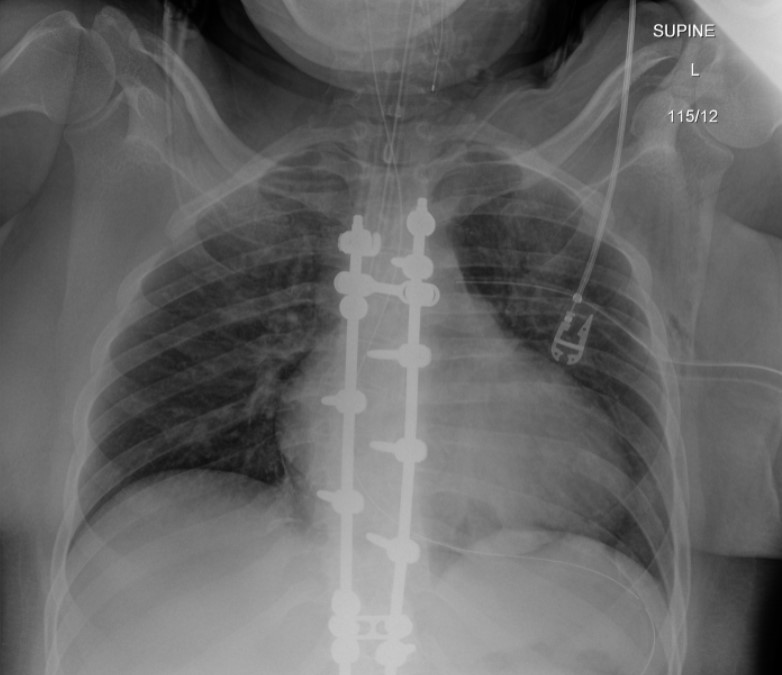

Postintubation radiograph (Figure 3) showed resolution of the retrocardiac mass with normal appearance of the diaphragm contour.

- Positive pressure ventilation can reduce the herniated viscera into the abdominal cavity and conceal the radiographic findings of a diaphragmatic injury.